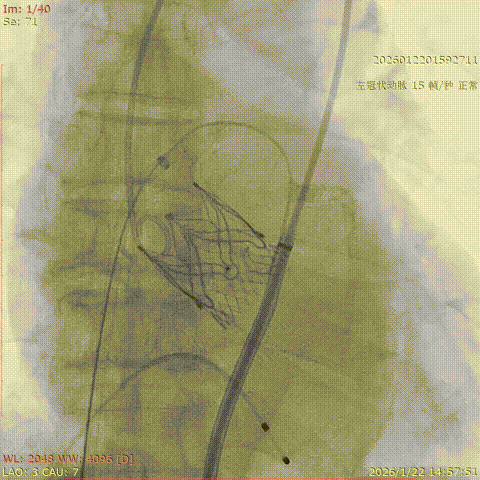

2026年伊始,TaurusTrio经导管主动脉瓣系统在复旦大学附属中山医院,浙江大学医学院附属第二医院,中国医学科学院阜外医院,首都医科大学附属北京安贞医院,四川大学华西医院等多家临床中心成功开展上市后全国首批植入。这不仅是TaurusTrio正式走向广泛临床应用的重要里程碑,更标志着中国单纯主动脉瓣反流介入治疗正式迈入了“心键合璧”的全新纪元。